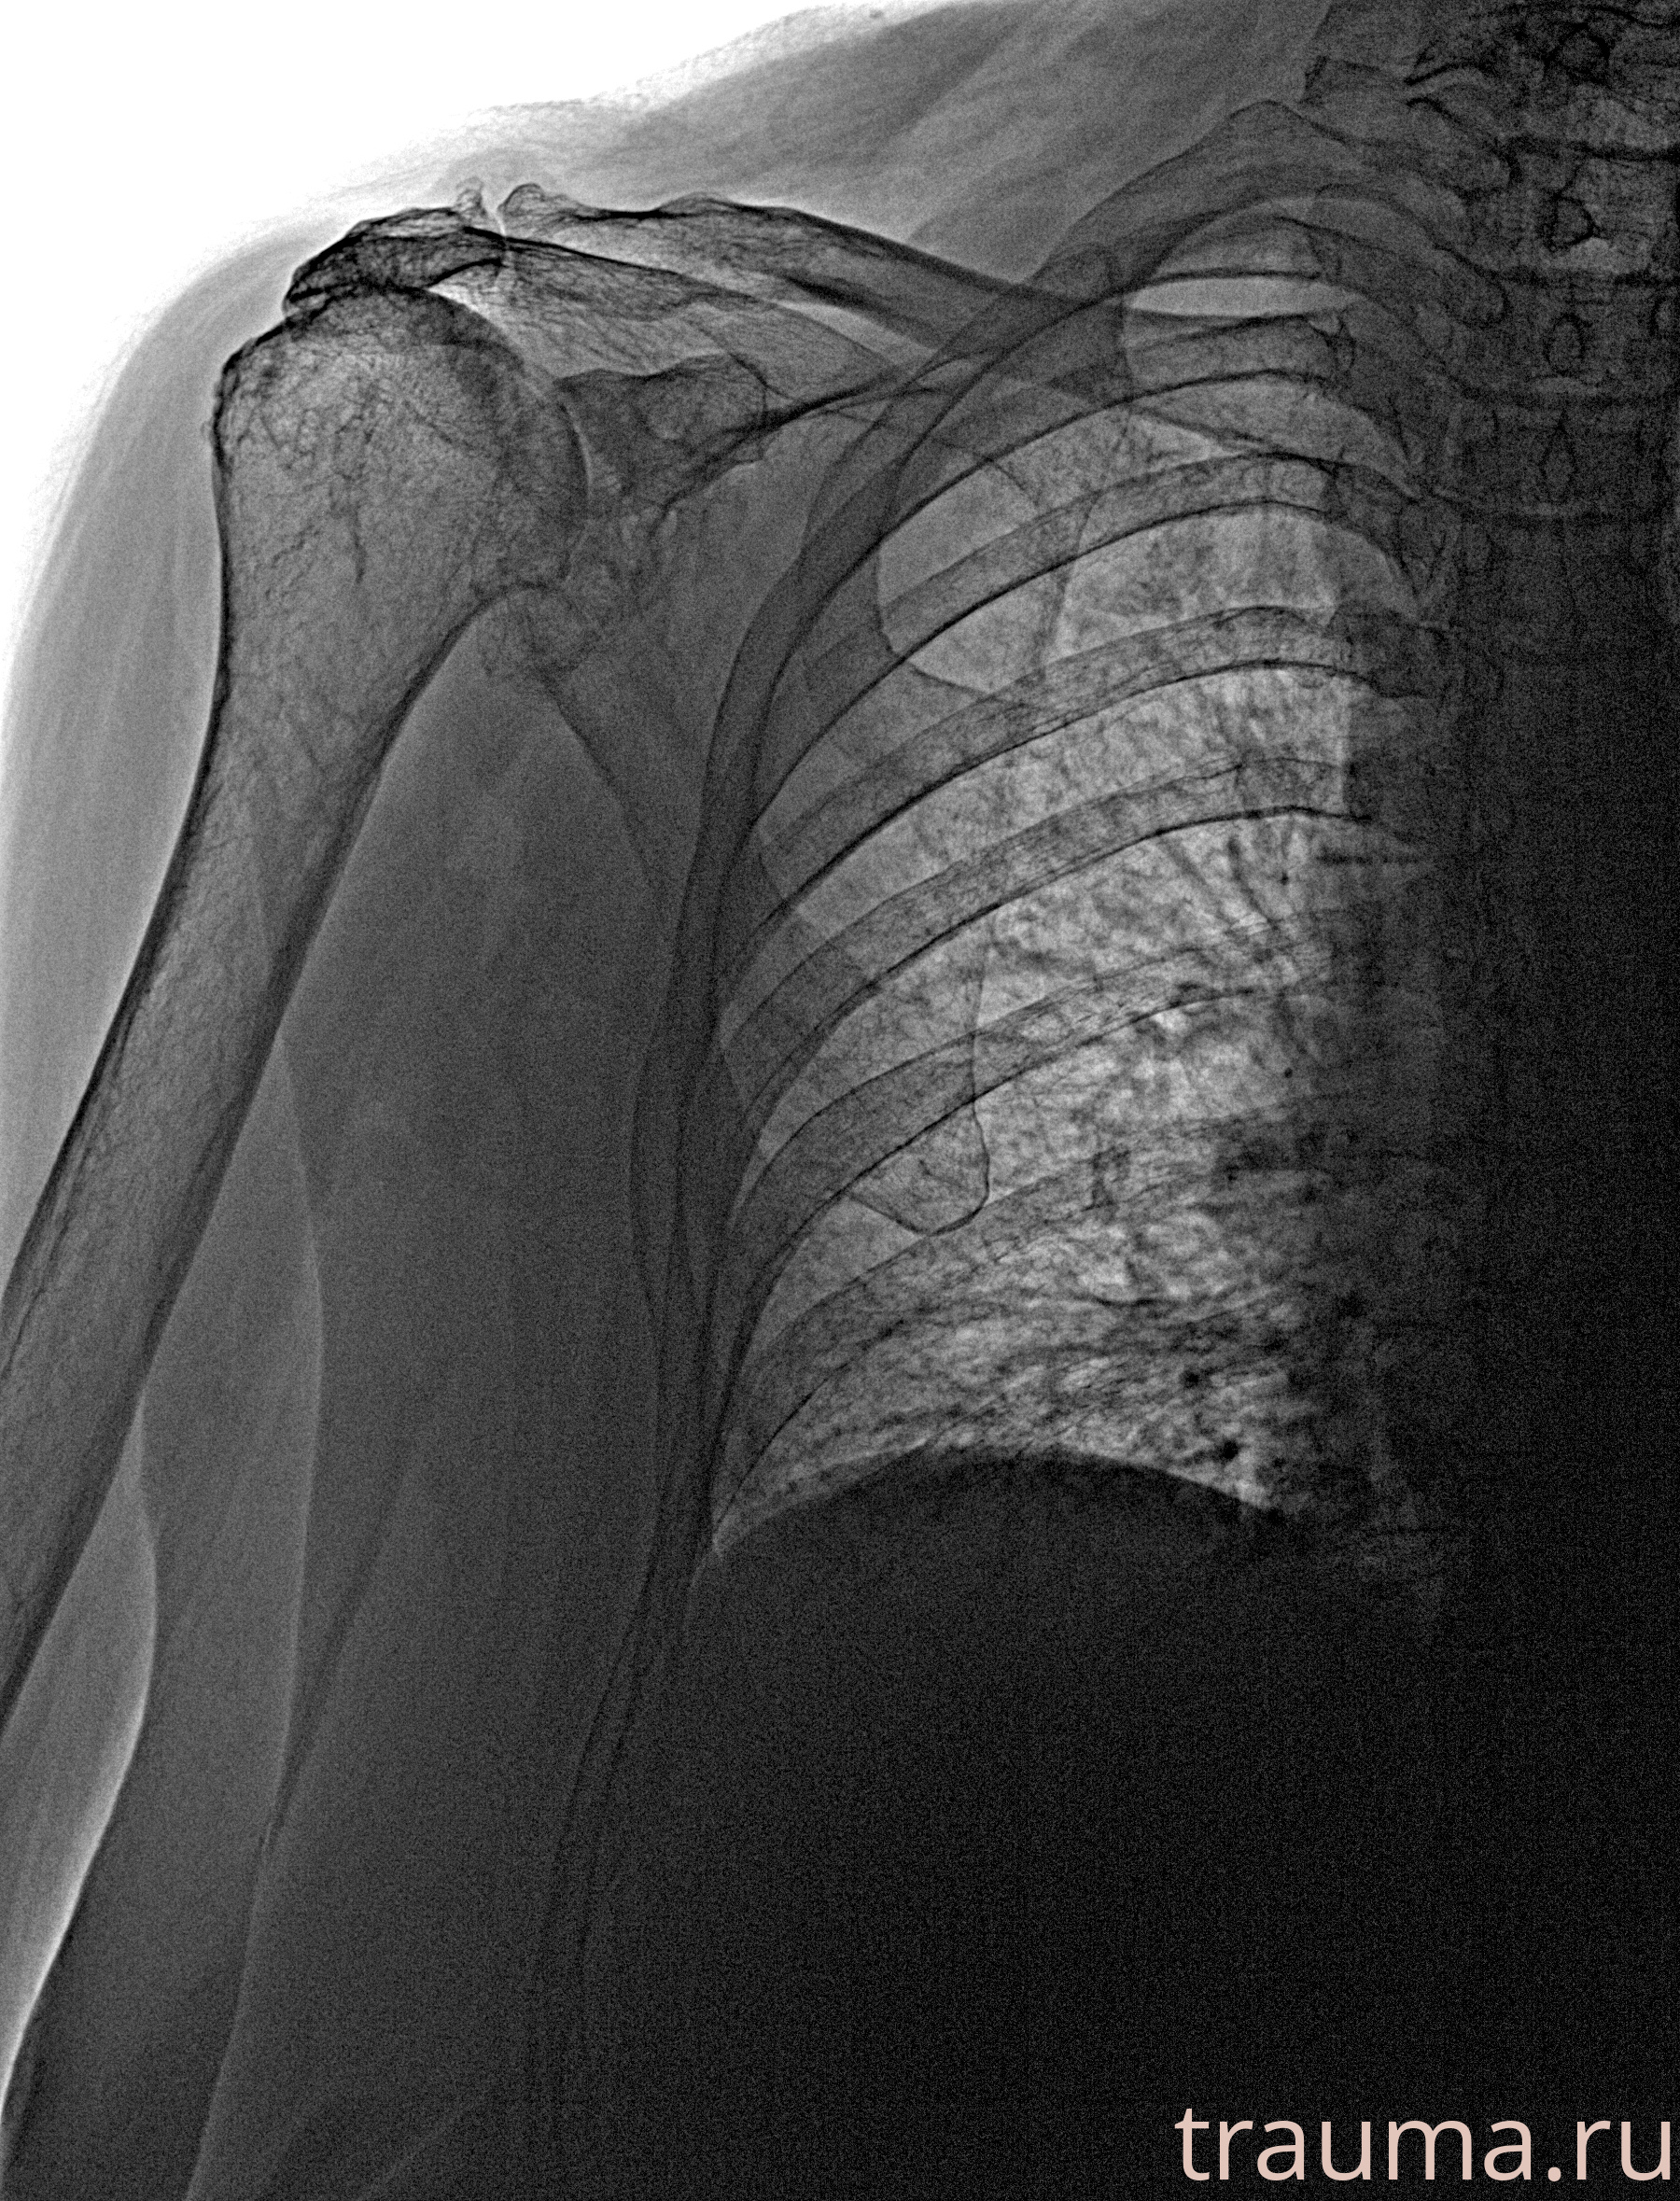

Рентгенограммы

Рентген на дому: по вашему адресу приезжает врач-рентгенолог, травматолог-ортопед с мобильным рентгеновским аппаратом, проводит диагностику травмы или заболевания, делает необходимые рентгенограммы, дает рекомендации по дальнейшему лечению. Получить качественные снимки в домашних условиях возможно благодаря уникальной методике, разработанной МосРентген Центром для института  Склифосовского